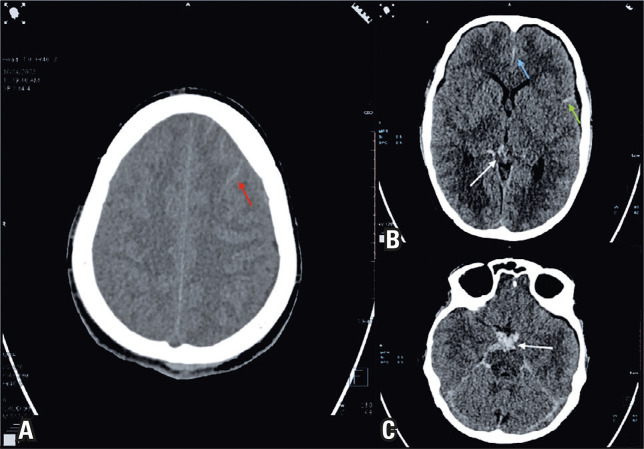

登革热是一种由黄热病病毒属成员引起的病媒传播急性发热性疾病,在全球的发病率急剧上升。登革热的神经系统并发症从 2.63%到 40%不等,蛛网膜下腔出血是一种罕见但重要的表现。嗜血细胞淋巴组织细胞增多症是一种危及生命的高炎症综合征,有时继发于登革热等感染。本报告介绍了一例严重登革热伴蛛网膜下腔出血和嗜血细胞淋巴组织细胞增多症的罕见病例。一名 19 岁男性患者因发热和肌痛就诊 7 天,随后出现剧烈头痛和呕吐。初步检查发现患者有高热、肝脾肿大和全血细胞减少。腰椎穿刺经计算机断层扫描确认,显示费舍尔2级蛛网膜下腔出血,左前冠状动脉和前交通动脉交界处有一个小动脉瘤。根据 2004 年的标准,继发性嗜血细胞淋巴组织细胞增多症被诊断为炎症指标升高、高甘油三酯血症和高铁蛋白血症。患者接受了静脉输液、渗透性利尿剂、抗癫痫药、类固醇和尼莫地平等保守治疗。患者的临床症状有所改善,并于第 11 天出院。孤立的蛛网膜下腔出血在登革热中很少见。嗜血细胞性淋巴组织细胞增多症的高炎症状态往往因症状不特异而被忽视,它可导致动脉瘤形成和破裂。对于伴有神经系统并发症的重症登革热患者,持续发热、全血细胞减少和高铁蛋白血症应引起对嗜血细胞淋巴组织细胞增多症的怀疑。对于严重登革热并发颅内出血的患者,临床医生应继续警惕嗜血细胞淋巴组织细胞增多症,以降低相关的发病率和死亡率。

Dengue, a vector-borne acute febrile illness caused by members of the Flavivirus genus, has dramatically increased its occurrence worldwide. Neurological complications of dengue range from 2.63 to 40%, and subarachnoid hemorrhage is a rare, but significant manifestation. Hemophagocytic lymphohistiocytosis is a life-threatening hyperinflammatory syndrome, sometimes secondary to infections such as dengue. This report presents a rare case of severe dengue with subarachnoid hemorrhage and hemophagocytic lymphohistiocytosis. A 19-year-old male presented with a 7-day history of fever and myalgia, followed by severe headache and vomiting. Initial examination revealed high fever, hepatosplenomegaly, and pancytopenia. Lumbar puncture confirmed via computed tomography showed a Fisher Grade 2 subarachnoid hemorrhage with a small aneurysm at the junction of the left anterior coronary and anterior communicating arteries. Secondary hemophagocytic lymphohistiocytosis was diagnosed based on the criteria from 2004, with elevated inflammatory markers, hypertriglyceridemia, and hyperferritinemia. The patient was treated conservatively with intravenous fluids, osmotic diuretics, antiepileptics, steroids, and nimodipine. The patient showed clinical improvement and was discharged on the 11th day. Isolated subarachnoid hemorrhage is rare in dengue. The hyperinflammatory state in hemophagocytic lymphohistiocytosis, which is often overlooked due to nonspecific symptoms, can lead to aneurysm formation and rupture. Persistent fever, cytopenia, and hyperferritinemia should raise suspicion of hemophagocytic lymphohistiocytosis in cases of severe dengue with neurological complications. In patients with severe dengue and intracranial hemorrhage, clinicians should remain cautious for hemophagocytic lymphohistiocytosis to reduce the associated morbidity and mortality.